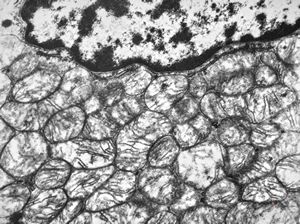

F, 45y. | carcinoid … liver metastasis